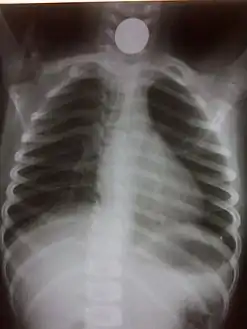

- Chest radiograph showing a Venezuelan 25 cent coin lodged in the upper esophagus of a 9-year-old girl.

- A coin seen on AP CXR in the esophagus

If the person who swallowed the foreign body is doing well, usually an x-ray image will be taken which will show any metal objects, and this will be repeated a few days later to confirm that the object has passed all the way through the digestive system. Also it needs to be confirmed that the object is not stuck in the airways, in the bronchial tree.